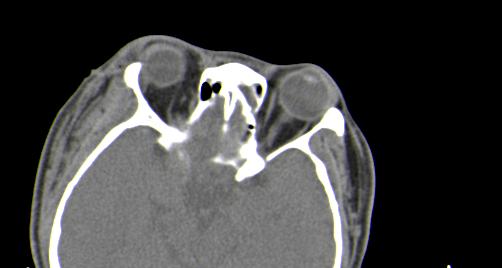

以下是引用皎皎白驹在2006-11-29 8:48:00的发言:[br]影像表现:双侧筛窦和上颌窦、鼻腔内均密度增高,右侧视神经增粗、弯曲,左筛窦顶部筛板及右侧纸板近视神经孔区可见骨折线。[br]结合临床表现考虑:右侧筛窦纸板近视神经孔区骨折致右侧视神经损伤。最好做个眼眶冠状扫描,更明确右侧视神经管是否狭窄。

以下是引用w_jianhua在2006-11-29 10:07:00的发言:[br]影像表现:双侧筛窦和上颌窦、鼻腔内均密度增高,右侧视神经增粗、弯曲,左筛窦顶部筛板及右侧纸板近视神经孔区可见骨折线。[br]结合临床表现考虑:右侧筛窦纸板近视神经孔区骨折致右侧视神经损伤。最好做个眼眶冠状扫描,更明确右侧视神经管是否狭窄。 [br] [br]支持[br]

以下是引用守望可可西里在2006-11-29 9:46:00的发言:[br][quote]以下是引用皎皎白驹在2006-11-29 8:48:00的发言:[br]影像表现:双侧筛窦和上颌窦、鼻腔内均密度增高,右侧视神经增粗、弯曲,左筛窦顶部筛板及右侧纸板近视神经孔区可见骨折线。[br]结合临床表现考虑:右侧筛窦纸板近视神经孔区骨折致右侧视神经损伤。最好做个眼眶冠状扫描,更明确右侧视神经管是否狭窄。